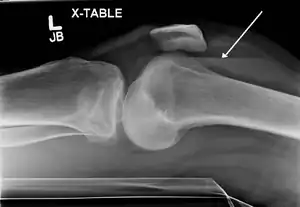

Lipohemarthrosis due to a tibial plateau fracture

A tibial plateau fracture seen on X-ray